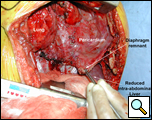

Through a 7th interspace right thoracoabdominal incision, the right lung was decorticated and pneumolysis performed (Figure 5). Once dissection was complete, the liver was found in the pleural space with only a small rim of diaphragm medially (Figure 6). The liver was completely mobilized and reduced into the abdomen, insuring that the right hepatic vein was not kinked. Multiple liver biopsies were obtained. The diaphragm was reconstructed using a 15x25cm 2mm thick polytetrafluoroethylene patch, anchoring it posteriorly near the 10-11th thoracic vertebral level to the posterior mediastinal fascia, laterally around the ribs, and anteriorly to the medial remnant of the diaphragm (Figure 7).